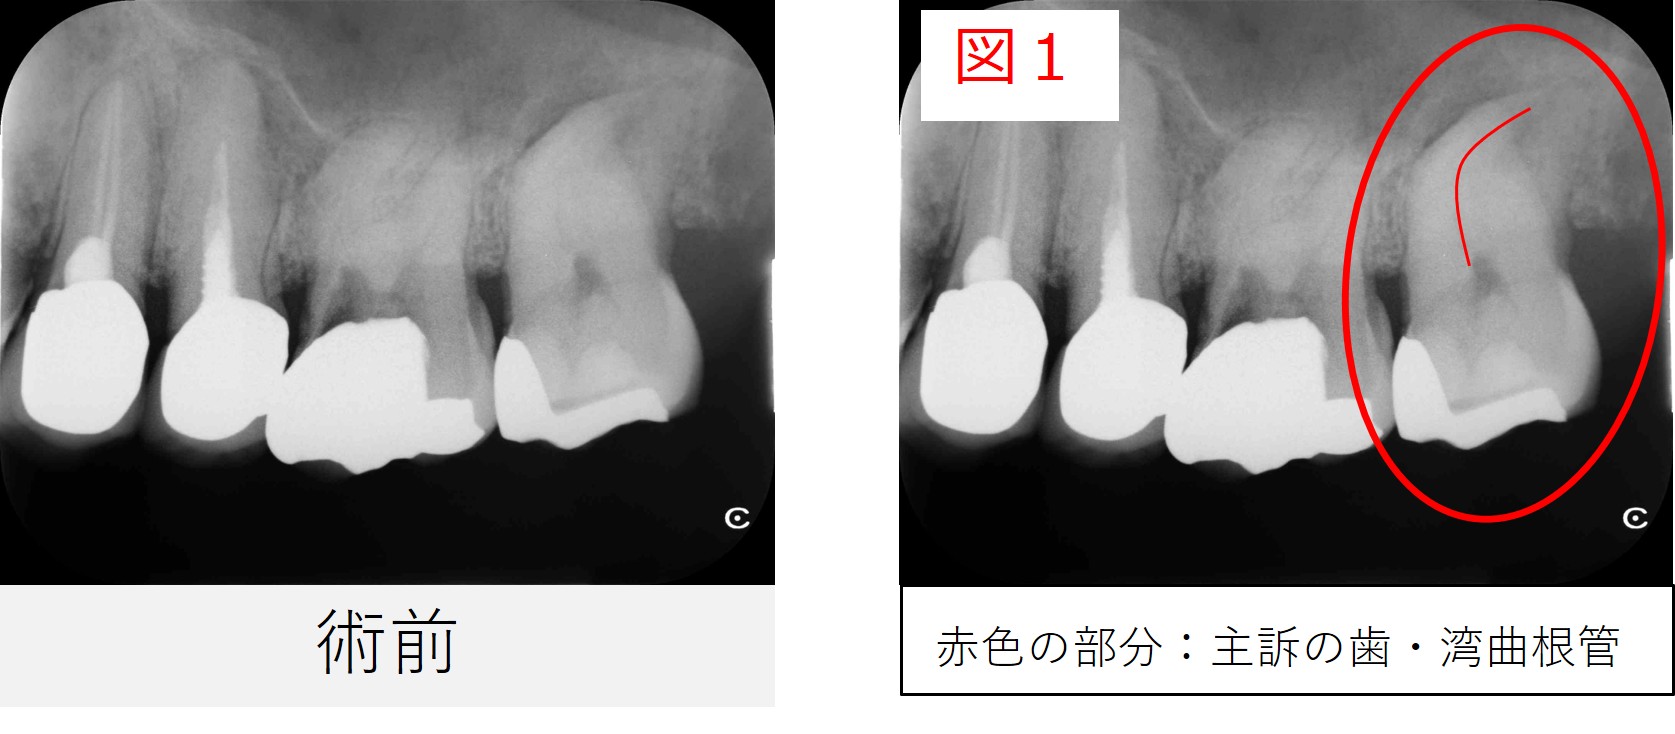

●レントゲン・CT画像所見

レントゲンおよびCT画像では、左上7番の根尖部に黒い影(骨のない部分)を認め、炎症が上顎洞(鼻と繋がっている空洞)にまで及んでいる所見が確認されました。

また、根管は強く湾曲しており、治療の難易度が高い症例でした。